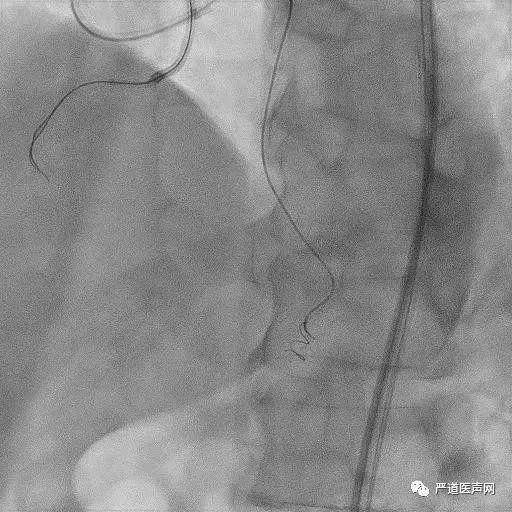

Retro: Corsair + Suoh 03

Delta Health Live Case Demonstration

Retro: Corsair + Suoh 03

Delta Health Live Case Demonstration

ADR: Stingray LP + GAIA Third

Delta Health Live Case Demonstration

ADR: Stingray LP + GAIA Third

Delta Health Live Case Demonstration

Final Results

Delta Health Live Case Demonstration